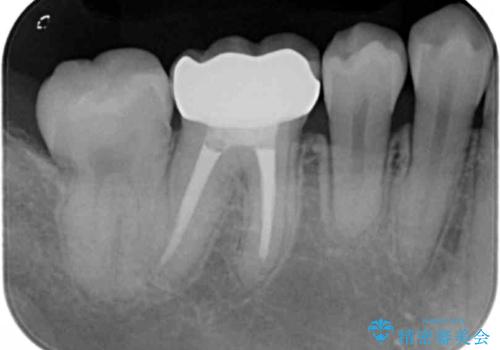

- 前歯のがたつきを主訴に来院。

右下の奥の銀歯も治療しています。

- 115.5万円 矯正治療 85万円、奥歯ジルコニアクラウン11万円(ZrCr 10万円、仮歯1万円、矯正用仮歯2万円)セラミックインレー7万円費用は治療当時の料金となります

下の前歯を下げるため、IPR(歯をわずかに削る処置)を行っています。